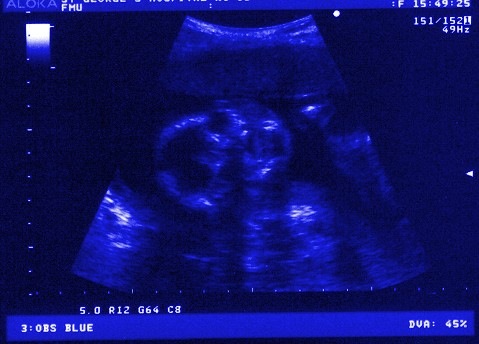

I took her to the doctor the next day. He gave her a pregnancy test that confirmed what we already knew, confirmed what the three pregnancy tests we had already taken said. She was pregnant. He guessed somewhere between 5 to 8 weeks, but wasn’t sure. He was worried about the pain, said she could be having an ectopic pregnancy. That scared us. As much as I wasn’t sure if I wanted to have a baby, I knew I didn’t want anything to be wrong with him/her.

The doctor ran some test, said he was checking the levels of some hormone and we would have to come back in 48 hours for another test, and then we’d go from there. We left scared, holding each other. Tears ran down her cheek. I promised her it would be okay, although I knew that wasn’t a promise I could keep.

We never made it to see that doctor. The next day she collapsed in the bathroom. One look at the pain on her face, the blood that had stained her underwear, I knew she was having a miscarriage.